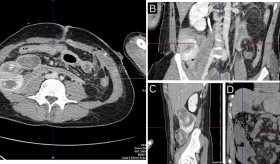

Diagnóstico y examen físico

El examen físico se centrará en revisar el esternón para detectar sensibilidad o hinchazón. Asimismo, se pueden dirigir movimientos de la caja torácica o de los brazos para desencadenar los síntomas.

Dado que los síntomas de esta afección son similares al de las enfermedades cardíacas, pulmonares, problemas gastrointestinales y la osteoartritis, dependiendo el riesgo de cada caso, se pueden realizar exámenes para descartarlas, como un electrocardiograma o radiografía de tórax.